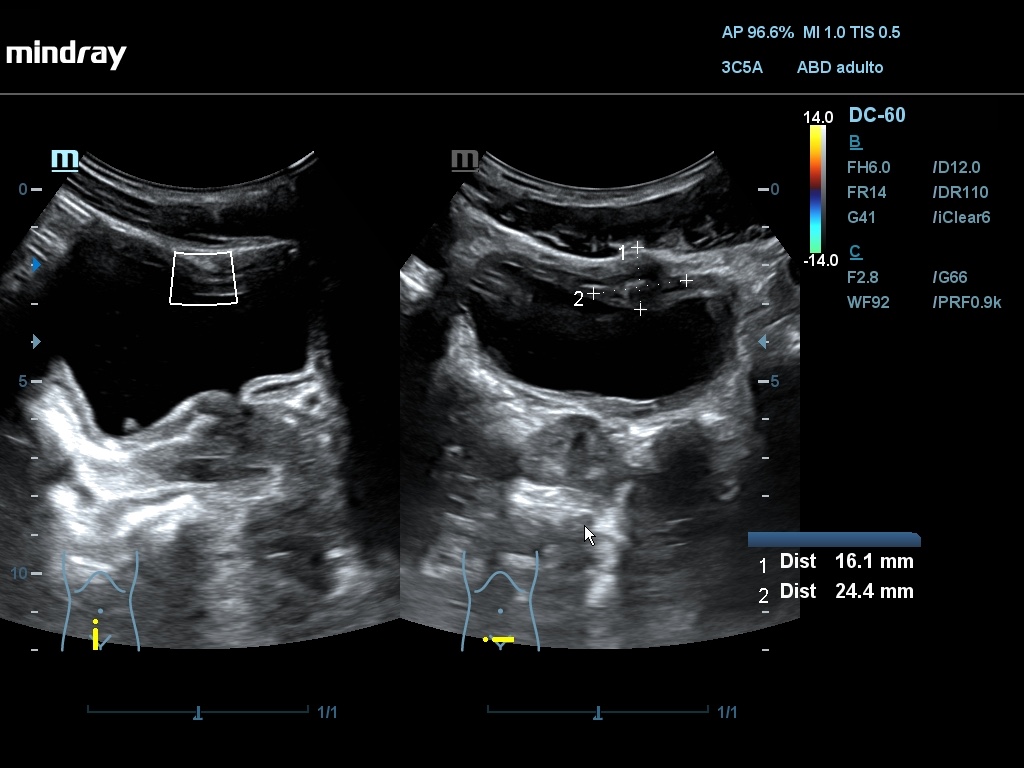

Ecografía: Se han observado varias imágenes poco habituales en vejiga urinaria: imágenes hiperecogénicas flotantes sin sombra posterior, móviles (detritus), engrosamiento de pared vesical que simula una vejiga no distendida con áreas anecoicas, pared con imagen en doble carril, masa vesical.

La sospecha inicial por criterios epidemiológicos es esquistosomiasis con afectación de vejiga urinaria. El diagnóstico diferencial se debe hacer con otras infecciones y tumores (raros en esta edad). En uno de los casos, AE considera que las imágenes se deben a vejiga poco replecionada y no las valora como patológicas. La masa vesical podría ser de tipo inflamatorio o tumoral.